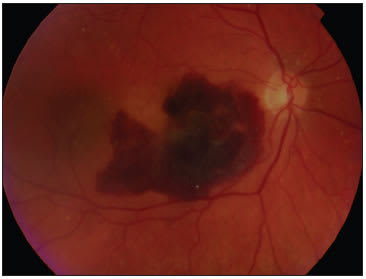

Management of subfoveal hemorrhage in age-related macular degeneration (AMD) is a challenging and difficult situation for the patient and the surgeon. How disheartening to look inside an eye to find a large clot of blood under the fovea, particularly after other treatments have already been initiated. Such a clot is a sign of submacular hemorrhage and occult choroidal neovascularization (CNV).

Even worse is the devastating loss of vision for the patient. Such patients carry an extremely poor prognosis. In this hopeful day of anti-vascular endothelial growth factor (VEGF) therapy, an easy fix for those patients with subretinal bleeds from AMD and devastating visual loss is yet to be found.

Treatment with anti-VEGF medication treats the CNV component without removing the blood. If the hemorrhage is thick, the blood remains (eg, see Figures 1 and 2). There are no studies published to date to determine visual outcomes for this subset of AMD patients with large subretinal hemorrhages. Photodynamic therapy has been attempted for submacular hemorrhage in AMD.10 Once again, the case series are too small to draw conclusive evidence of success. This method does not remove the blood. Interestingly, PDT carries a small risk of causing submacular hemorrhage, as seen in a case report of submacular hemorrhage following PDT treatment.11

Of course not all submacular hemorrhages are created equal. They come in all shapes and sizes and depths. The available natural history studies did not classify the extent of hemorrhage in the small-case analysis. Presumably, small thin hemorrhage under the fovea most likely would have a far better prognosis than the dense choroidal hemorrhage with serous retinal detachment.

Also, baseline vision should be considered. For example, one patient with a dense central scar with a new

submacular hemorrhage would not have benefitted from surgical intervention. Likewise, a chronic subfoveal hemorrhage where dehemoglobinized blood was seen would most likely have already caused irreversible damage. In this case, surgical intervention would not have provided visual benefit.